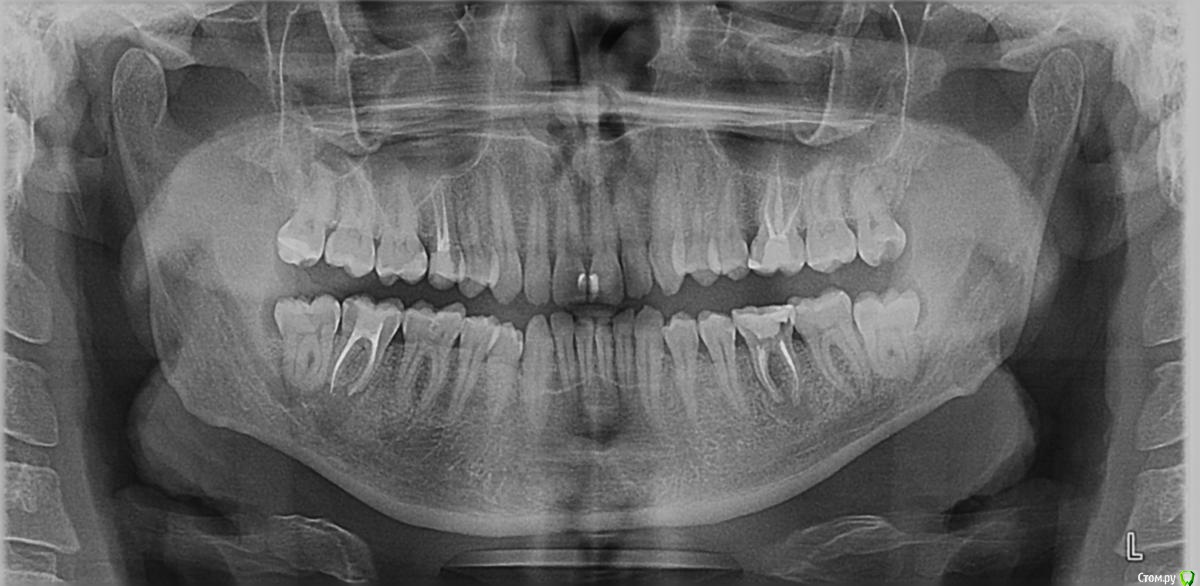

Constantine Опубликовано 28 января, 2019 Поделиться Опубликовано 28 января, 2019 (изменено) Здравствуйте, дамы и господа! В мае мне поставили циркониевую коронку на металлическую культевую вкладку (левая нижняя шестерка).Через месяц примерно образовался свищ под ней. Врач сказал полоскать содой - пройдет. Прошло. Еще через 2 месяца появилось ощущение, что коронка мешает немного. Пришел к врачу - он подпилил ее. Еще пару раз появлялись свищи. Говорил об этом врачу, он отвечал, что может быть перелом, но скорее всего все ок и нужно пополоскать содой. Несколько дней назад зуб под коронкой начал дико болеть. Пошел опять к врачу. Он сказал, что под корнем воспаление. Сделал надрез, почистил и отправил на КТ. Сделал КТ. Он говорит: "Хронический гранулирующий периодонтит. Есть два варианта: лоскутная операция с последующим плазмолифтингом или удаление. Но так как там полный трындец - лучше сразу удалять" Зуб до установки коронки не беспокоил (ничем кроме кариеса).Врач говорит, что проблема была скорее всего до установки коронки и он тут ни при чем.На вопрос, зачем же тогда ставили коронку, отвечает, что не видел ничего на снимках. Вопросов два:Как понять, виноват ли мой нынешний врач, ставивший коронку, или врач, который изначально пломбировал каналы? Что делать? Пробовать спасать зуб? Или уже позняк метаться и только рвать? На панорамном снимке - зуб до коронки, на КТ - то, что сейчас. Благодарю! Изменено 28 января, 2019 пользователем Constantine Ссылка на комментарий